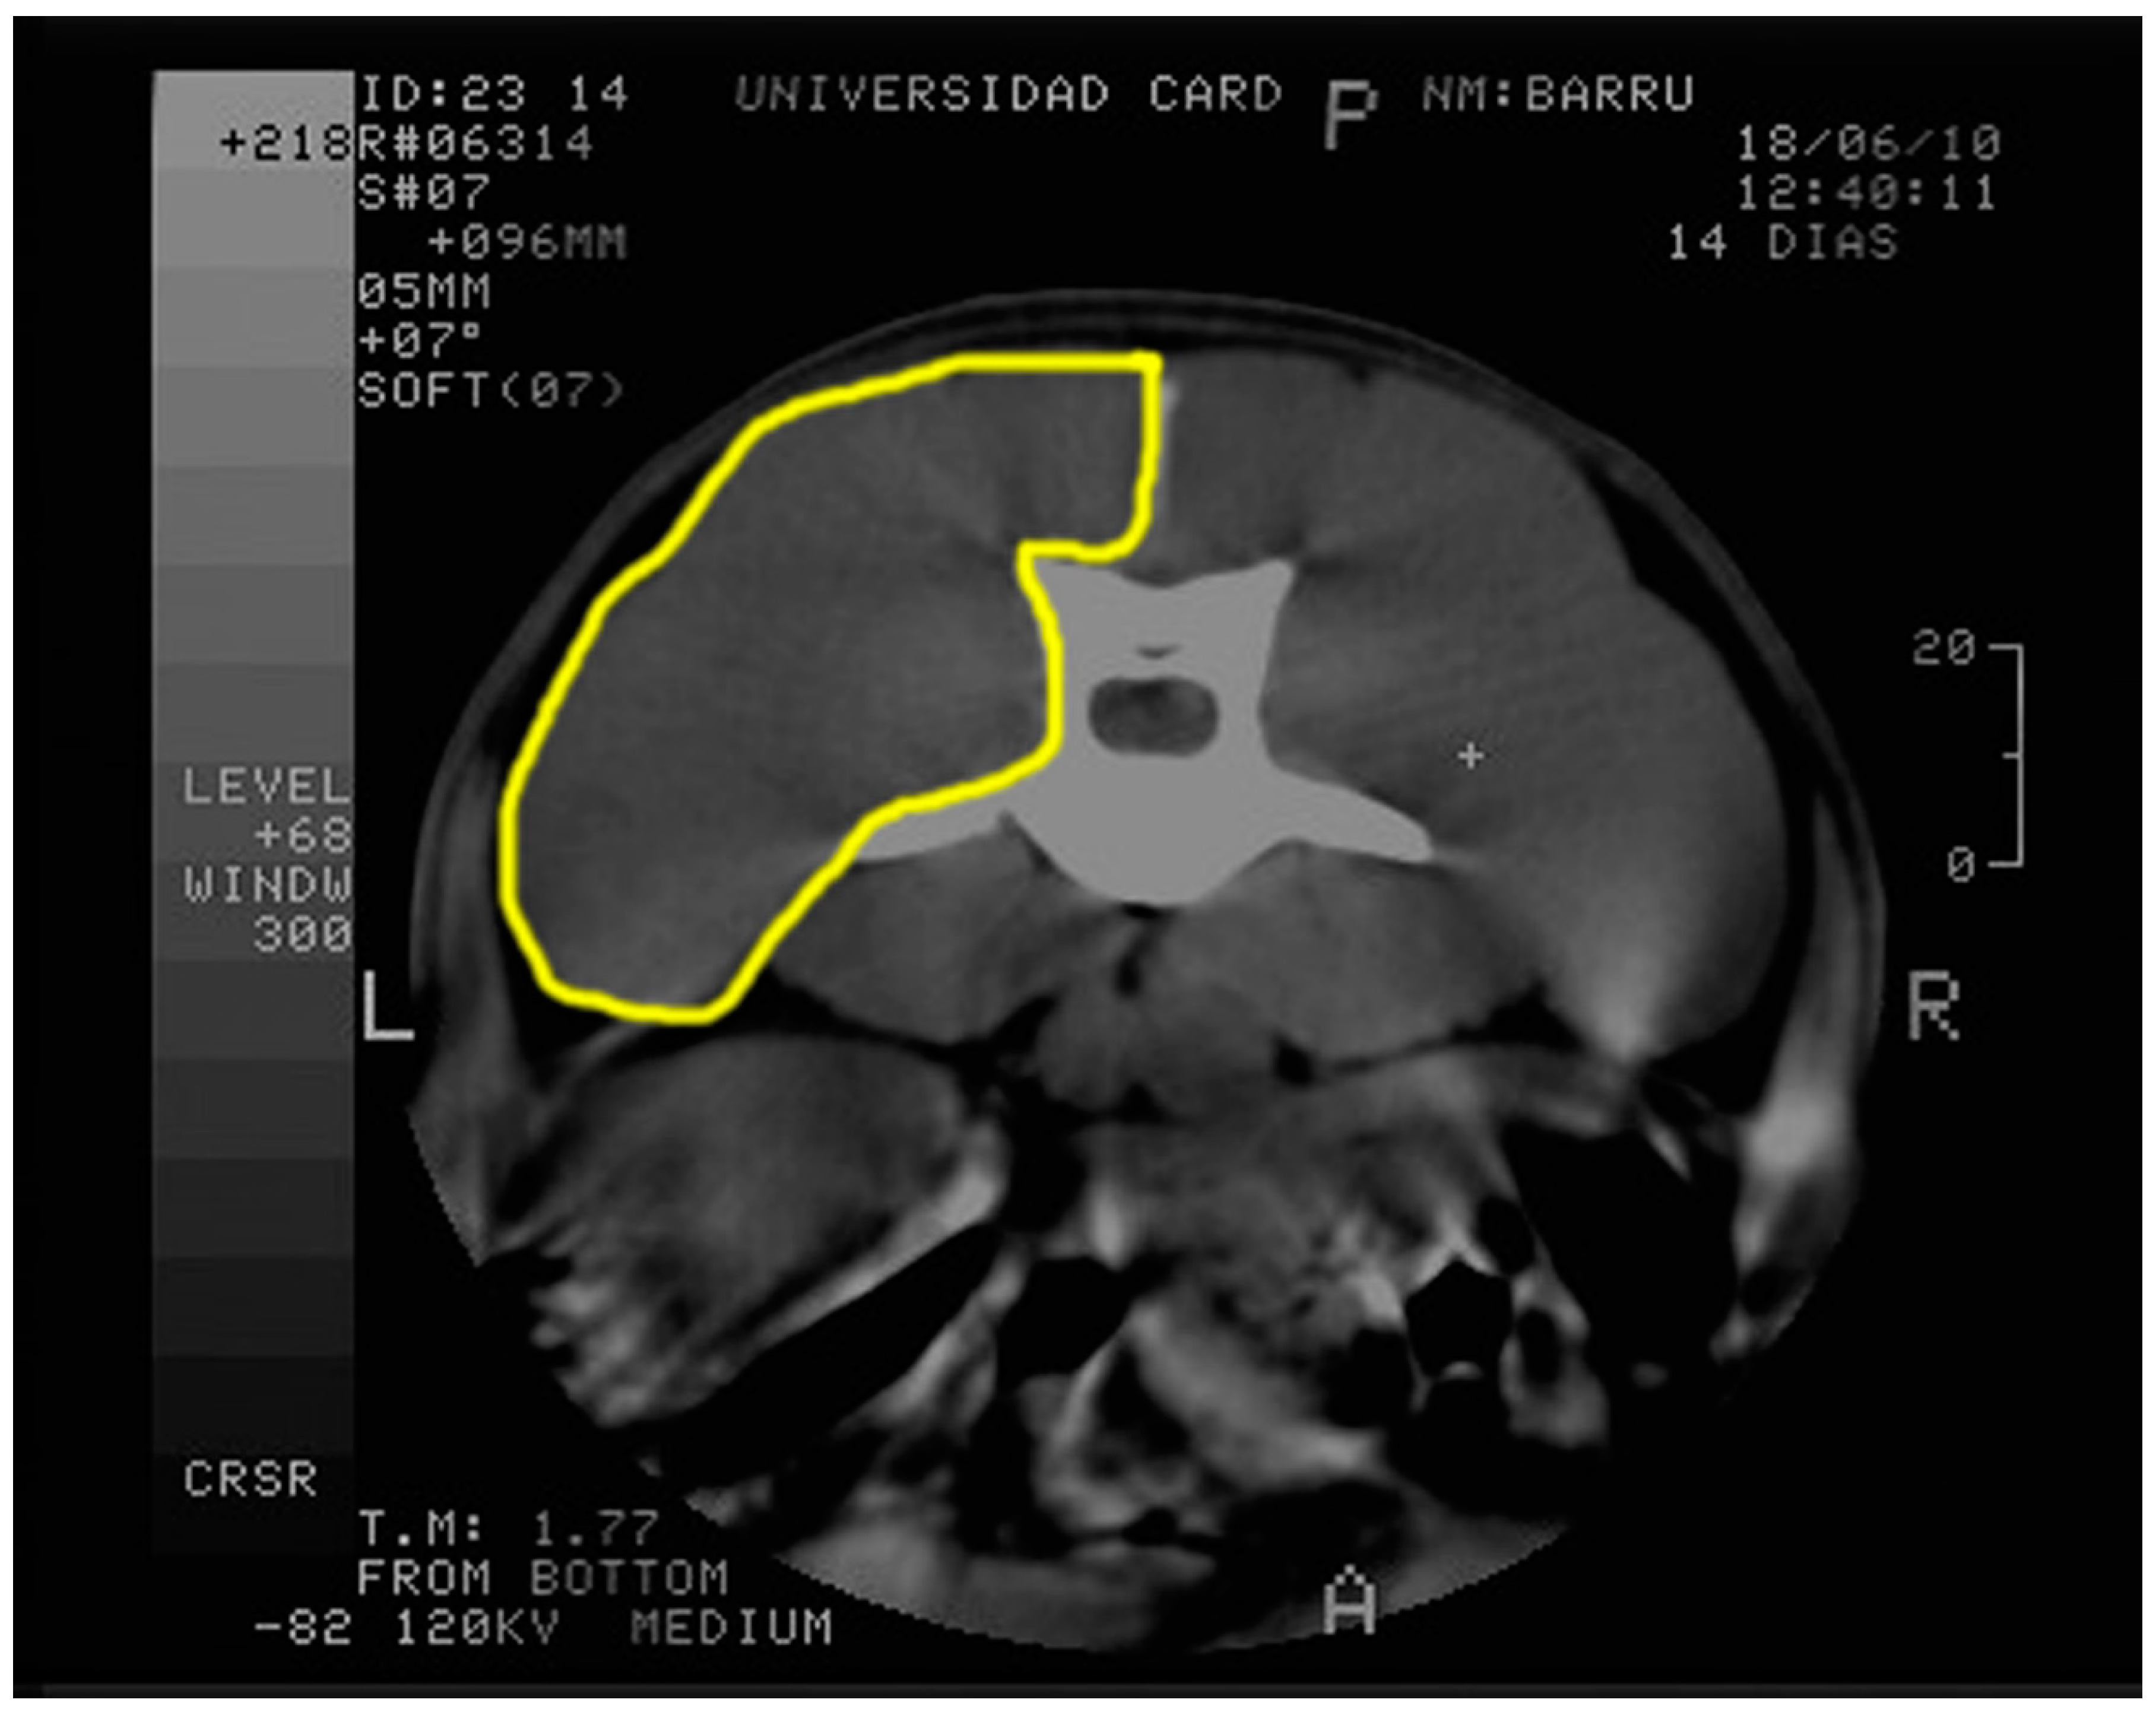

2.3. Computed Tomography and Echography Evaluation

4.6. Image Processing